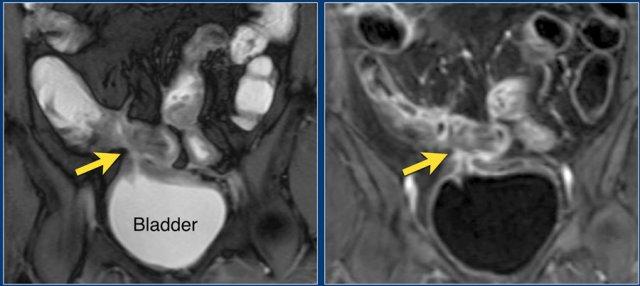

Hình ảnh cho thấy hồi tràng cuối với kiểu ngấm thuốc đồng nhất, mức độ vừa (mũi tên xanh lá) và mạnh (mũi tên đỏ) trên hình ảnh T1 axial sau tiêm thuốc tương phản từ.

Hình ảnh là ảnh T1 sau tiêm thuốc tương phản từ với kiểu ngấm thuốc niêm mạc tại hồi tràng cuối (mũi tên).

Kiểu ngấm thuốc phân lớp tại trực tràng kèm một ít mờ mỡ xung quanh trên hình ảnh T1 axial sau tiêm thuốc tương phản từ (mũi tên). Tình trạng viêm liên tục với kiểu ngấm thuốc đồng nhất có thể thấy tại đại tràng sigma (mũi tên xanh lá). Ngoài ra, có một nang phần phụ bên phải với viền ngấm thuốc (đầu mũi tên).